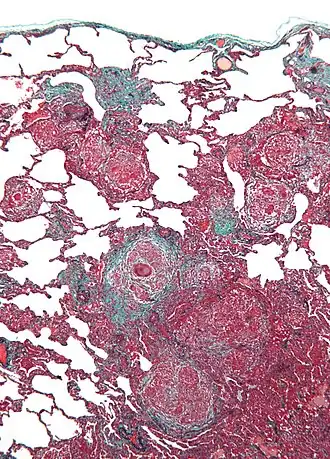

![]() Micrografía de neumonitis por hipersensibilidad, la histología corresponde a un pulmón de cuidador de aves. Biopsia de pulmón . Tinción tricrómica. | ||

El pulmón de cuidador de aves es un tipo de neumonitis por hipersensibilidad. Está provocado por la exposición a proteínas de origen aviar presentes en el polvo seco de los excrementos y a veces en las plumas algunos pájaros. Los pulmones se inflaman, se forman granulomas. Se han implicado pájaros como las palomas, periquitos, cacatúas, loros, tórtolas, los pavos y los pollos.

Un diagnóstico definitivo puede ser difícil de conseguir sin una prueba invasiva, pero la exposición extensa a las aves combinada con la capacidad de difusión disminuida es fuertemente sugestiva de esta enfermedad. La radiografía o tomografía muestran cambios físicos en la estructura de pulmón (patrón de vidrio esmerilado) con el progreso de la enfermedad. La distribución precisa y los tipos de daño de tisular difieren entre enfermedades similares, al igual que la respuesta a tratamiento con prednisona. Hay dos formas de pulmón de cuidador de aves: la aguda y la crónica. El daño alveolar difuso (DAD) puede cursar con insuficiencia respiratoria aguda; la fibrosis intersticial es típica de la forma crónica.[2] En ambos, la respuesta inflamatoria subyacente se detiene tras la exclusión del alérgeno, pero los síntomas pueden persistir según el grado de daño sufrido.[2] Entre los procedimientos invasivos, lavado broncoalveolar típicamente muestra linfocitosis prominente con una proporción CD4+/CD8+ invertida, y la biopsia de pulmón normalmente revela inflamación con granulomas no necrotizantes.[2]